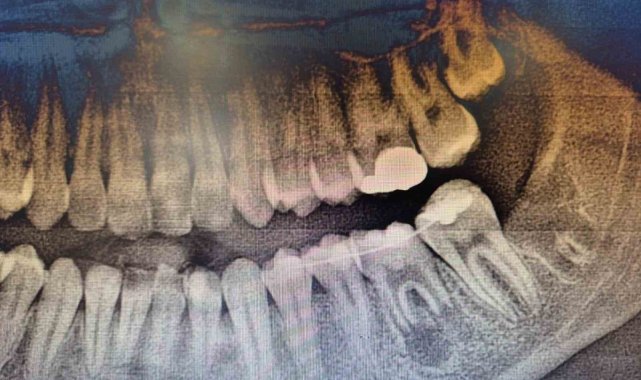

İleri düzey çürük nedeniyle daimi azı dişi çekilen hastaya, yaşı gereği çene gelişimi devam ettiği için klasik implant tedavisi uygun görülmedi. Bunun yerine, hastanın ağzında gömülü halde bulunan yirmi yaş dişi, uzman ekip tarafından cerrahi operasyonla çıkarılarak çekilen dişin yerine nakledildi.

Operasyon sırasında, dişin sağlıklı bir şekilde tutunmasını sağlamak için hastanın kendi kanından elde edilen PRF (Platelet Rich Fibrin) materyali, nakil öncesi hazırlanan diş yuvasına yerleştirildi. Bu uygulama, doku iyileşmesini hızlandıran ve hücre yenilenmesini destekleyen doğal bir yöntem olarak öne çıkıyor. Bu tedavi yöntemi, hastanın kendi dişi kullanıldığı için doğal görünüm, uyum ve fonksiyon açısından büyük avantaj sağlıyor. Aynı zamanda, vücut tarafından kabul edilme oranı yüksek olduğundan, uzun vadeli başarı şansı da oldukça yüksek.